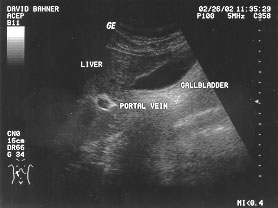

Hepatorenal space (labeled)